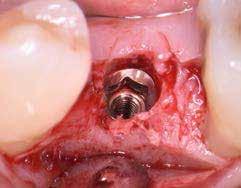

A részleges extrakció befejezése után következhet az implantátumágy preparálása a gyártó utasításai szerint (6.

kép). A bemutatott esetben Nobel Replace CC 4,3x13mm implantátumot helyeztünk be, amely a bukkális oldalon direkt kontaktusba került a megmaradt foggyökérdarabbal (7. kép). Az alveolus oldalfalai és a körszimmetrikius implantátum közötti hézag kitöltésére bovin eredetű xenograftot (Creos S xenogain) használtunk (8. kép). A hasonló

6. kép: Implantátum-ágy preparáció. 7. a–b. képek: Implantátum behelyezés. 8. kép: A behelyezett implantátum. 10. a–b képek: Azonnali ideiglenes korona készítése. 9. kép: Megfelelő primer stabilitás.